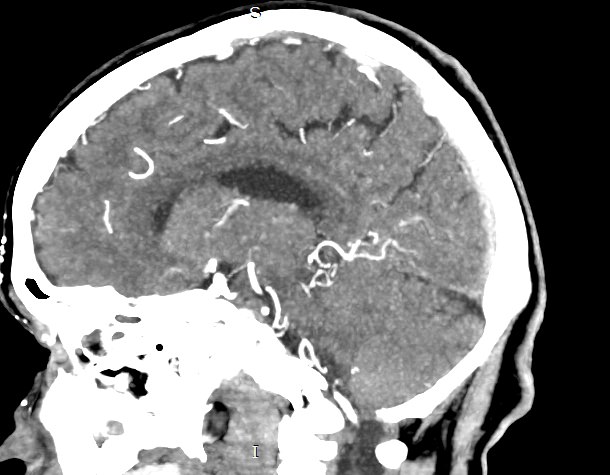

Мультиспиральная компьютерная томография головного мозга относится к лучевым методам исследования и основана на использовании проникающей способности рентгеновских лучей, которые в различной степени поглощаются органами и тканями. Степень поглощения зависит от плотности анатомических структур, благодаря чему можно получить подробные изображения внутренних органов. Во время исследования трубка томографа вращается вокруг пациента и производит снимки поперечного сечения, что позволяет детально визуализировать кости черепа и все структуры головного мозга.

Для улучшения видимости внутричерепных структур применяется методика внутривенного болюсного контрастирования. Во время проведения КТ пациенту в вену вводится йодсодержащее контрастное вещество. Контраст с током крови попадает в патологически измененные участки ткани и очаги, что на снимках придает им яркие отличительные признаки по сравнению с окружающими здоровыми тканями. Контрастирование, в первую очередь, помогает в диагностике опухолевых процессов на ранних стадиях, когда лечение может дать наилучший результат.

В наших медицинских центрах КТ головного мозга с контрастированием проводится на новейших мультиспиральных компьютерных томографах экспертного уровня TOSHIBA AQUILION в различных модификациях. Аппараты снабжены увеличенным количеством сверхчувствительных детекторов, что позволяет при сканировании выполнять множество срезов поперечного сечения с минимальной толщиной среза от 0,5 мм. В результате получаются изображения исследуемой зоны в мельчайших подробностях, которые затем с помощью инновационных цифровых приложений преобразуются в трехмерные пространственные модели головного мозга для более точной диагностики. Помимо высокого качества изображений увеличенное количество детекторов обеспечивает быстроту выполнения сканирования, что значительно снижает уровень рентгеновского облучения для пациента во время обследования.